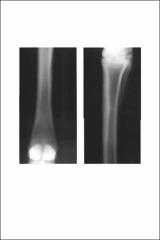

A two year old Quarter Horse gelding presented for evaluation of a previous vague lameness in the left hind leg. The horse was not lame at presentation. A radiographic survey of the tarsal and metatarsal region was made.The lateral-medial view shows a linear radiolucency coursing 'from proximal to distal within the dorsal cortex of metatarsal three (MT3) at the junction of its proximal and rniddle thirds. This lucency is identified as a vertically oriented line in the dorsoplantar view. At the endosteal level there is a slight bulging effect to the endosteal contour, but the margin is distinct. Additional oblique views and bright light viewing did not reveal associated soft tissue swelling or periosteal new bone. It is noted that the typical nutrient foramen is absent in the plantar cortex.